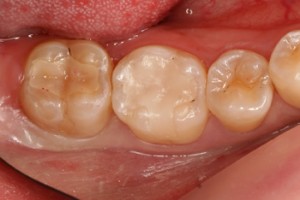

■口の中の金属を白くする症例

セット後![]() |

これで健康的な口元になり、大きく口を開けて笑った写真も気になりません。